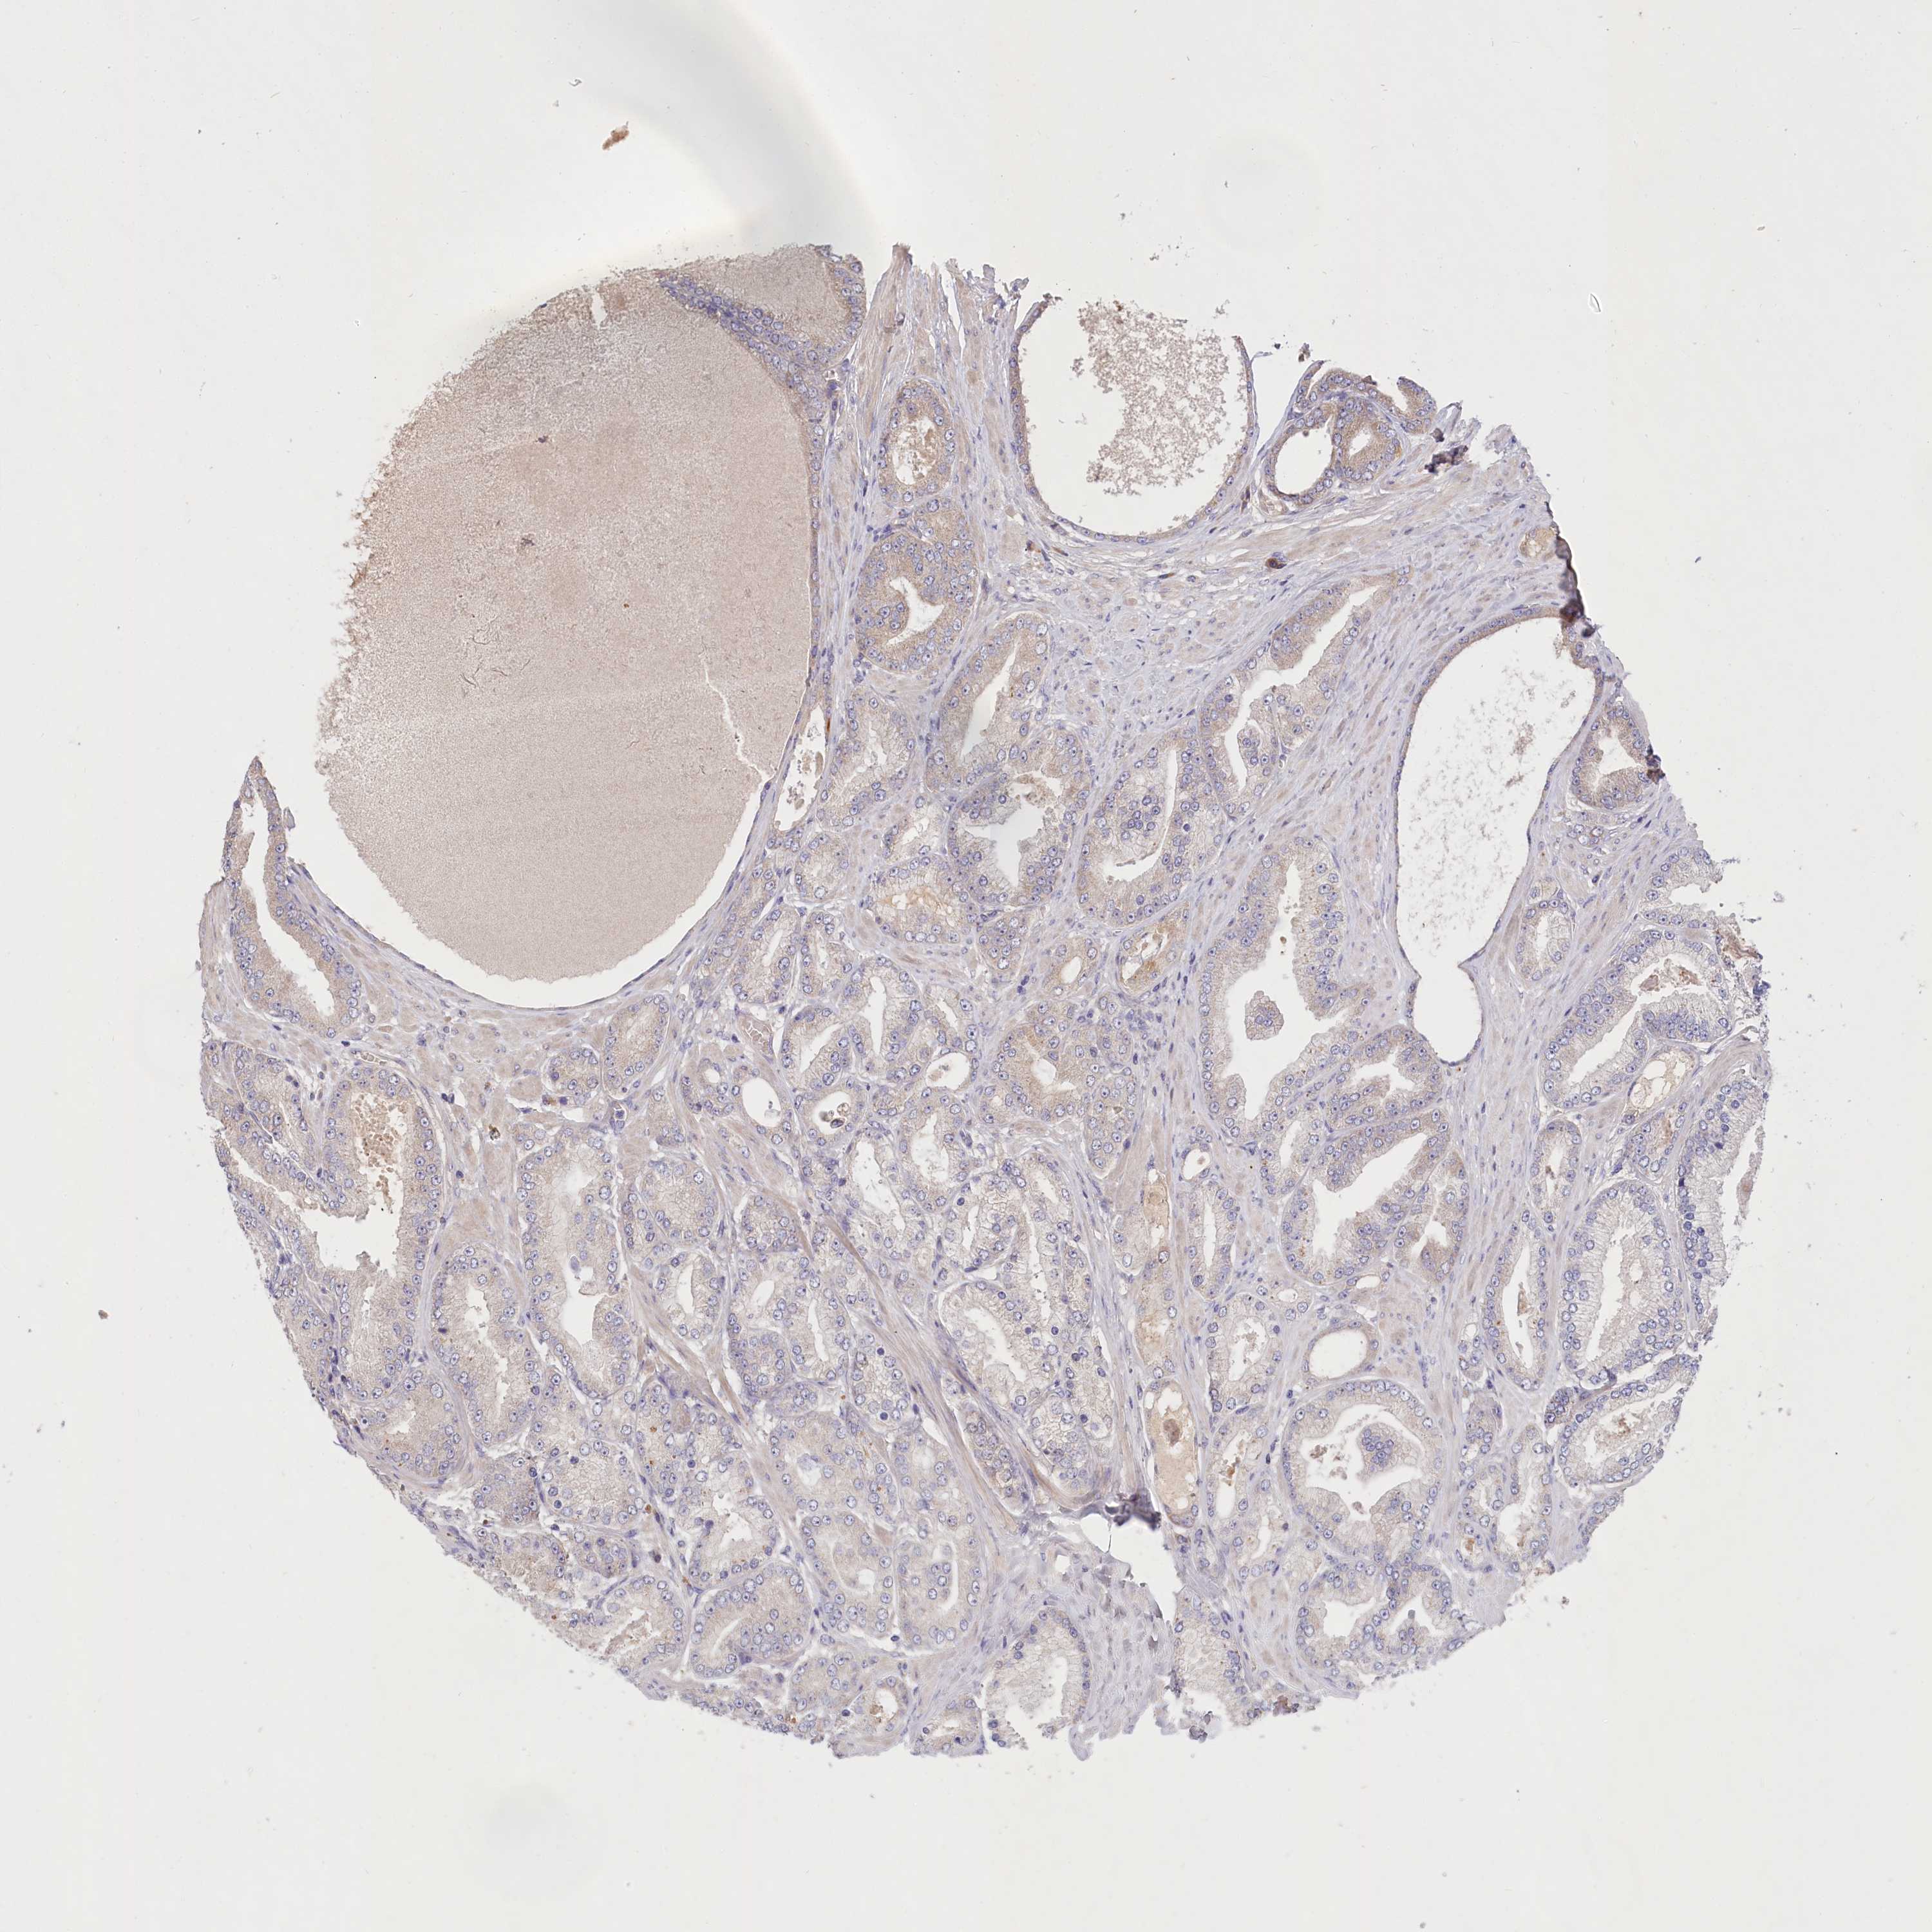

PROSTATE CANCER - Protein expressioni

A mouse-over function shows sample information and annotation data. Click on an image to view it in a full screen mode. Samples can be filtered based on level of antibody staining by selecting one or several of the following categories: high, medium, low and not detected. The assay and annotation is described here.

Note that samples used for immunohistochemistry by the Human Protein Atlas do not correspond to samples in the TCGA dataset.

Antibody stainingi

Antibody staining in the annotated cell types in the current human tissue is reported as not detected, low, medium, or high, based on conventional immunohistochemistry profiling in selected tissues. This score is based on the combination of the staining intensity and fraction of stained cells.

Each image is clickable and will lead to virtual microscopy that enables deeper exploration of all samples and also displays staining intensity scores, fraction scores and subcellular localization as well as patient and tissue information for each sample.

Antibody HPA038035

Antibody HPA038036

Staining

High

Medium

Low

Not detected

Intensity

Strong

Moderate

Weak

Negative

Quantity

>75%

75%-25%

<25%

None

Location

Nuclear

Cytoplasmic/membranous

Cytoplasmic/membranous,nuclear

Adenocarcinoma, NOS

Adenocarcinoma, High grade

Adenocarcinoma, Low grade